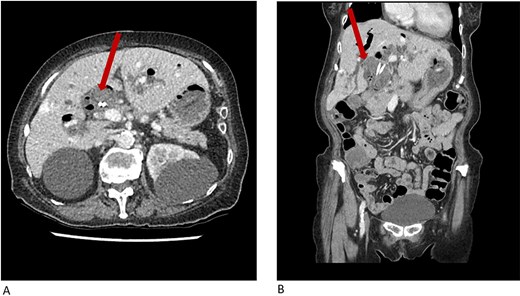

On examination, she was febrile (38.6°C) with otherwise normal vital signs. She had epigastric tenderness with guarding, was Murphy’s negative and non-icteric. Biochemistry revealed mildly deranged liver function and inflammatory markers: bilirubin 15 μmol/l, alkaline phosphatase 69 U/l, gamma-glutamyl transferase 18 U/l, alanine aminotransferase 65 U/l, aspartate aminotransferase 97 U/l, white cell count (WCC) 7.2 × 109U/l, and C-reactive protein (CRP) 71 mg/l. Computer tomography (CT) of the abdomen and pelvis showed CBD dilatation (30 mm) with peripheral enhancement and duodenal reflux (Fig. 1). An incidental hepatic haemangioma was also noted. Her presentation was consistent with cholangitis.

CT abdomen and pelvis showing common bile duct dilatation (arrow) with biliary stents in situ and incidental hepatic hemangioma in (A) axial plane and (B) coronal plane.